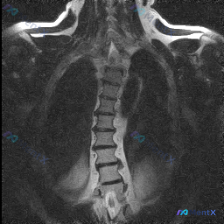

胸椎MRI发现轻度侧弯,下一步最关键的检查是什么?

整理到一份胸椎MRI冠状位T2加权的影像资料,先把核心阳性发现和阴性排查点列出来,大家看看思路会怎么走。

核心阳性表现:

- 胸椎整体存在轻度侧向弯曲,左右不对称

关键阴性排查(目前MRI层面):

- 脊髓信号正常,连续性好,无受压、增粗或中央管扩张

- 各椎体形态规则,骨髓信号均匀,未见压缩骨折、楔形变或局灶性异常信号

- 椎间隙高度尚可,无明显椎间盘塌陷

- 双侧小关节结构可见,无严重骨质增生

- 椎旁软组织对称,无肿胀、积液或占位

- 硬膜外腔无异常信号或占位效应

📋答案:综合影像学表现,该病例最可能为良性/生理性脊柱侧弯(特发性或姿势性可能性最高),退行性改变相关侧弯待排,先天性/发育性侧弯需进一步确认,隐匿性肿瘤或感染可能性极低但需警惕。